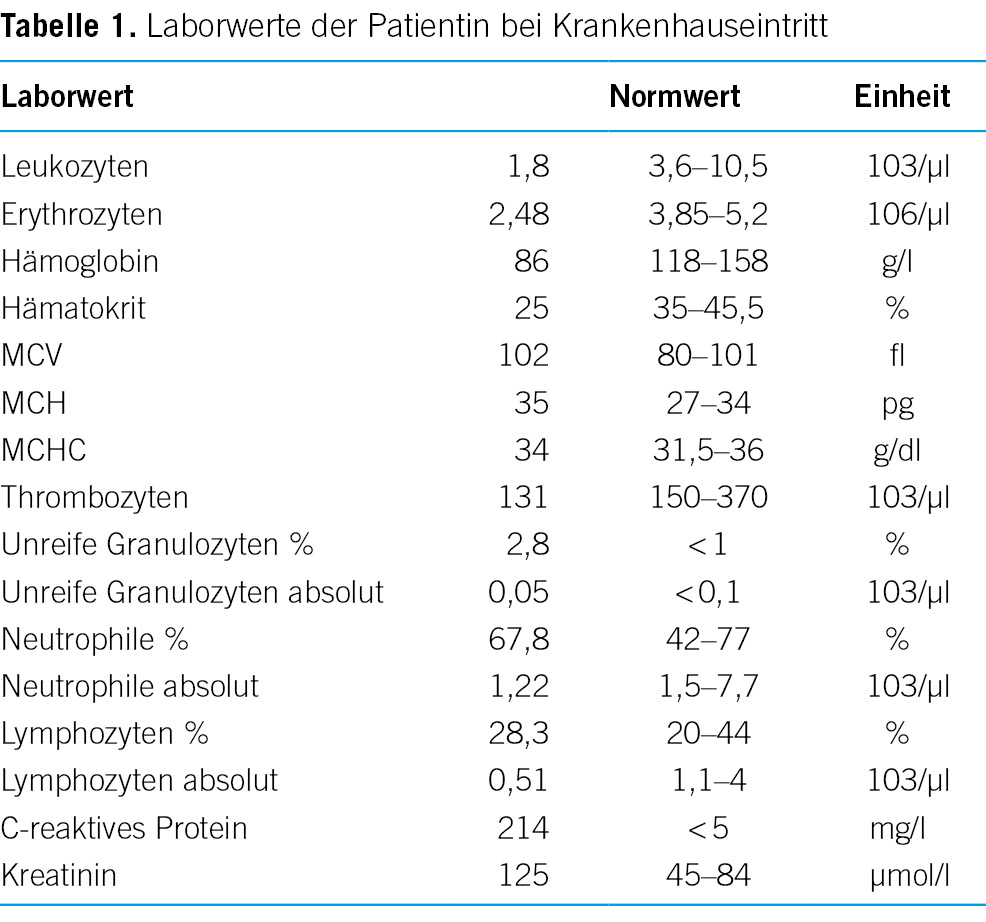

Bei Krankenhauseintritt präsentierte sich die Patientin grenzwertig hypoton (Blutdruck 107/68 mmHg), knapp normokard (Herzfrequenz 97/min) und afebril (Temperatur 37,0 °C) in leicht reduziertem Allgemein- und adipösem Ernährungszustand. In der klinischen Untersuchung fiel eine deutliche Druckdolenz im Unterbauch sowie eine Klopfdolenz paravertebral beidseits im Bereich der unteren Lumbalwirbelsäule auf. Laboranalytisch imponierten ein deutlich erhöhtes C-reaktives Protein von 214 mg/l (< 5 mg/l) sowie eine Panzytopenie (Tabelle 1).